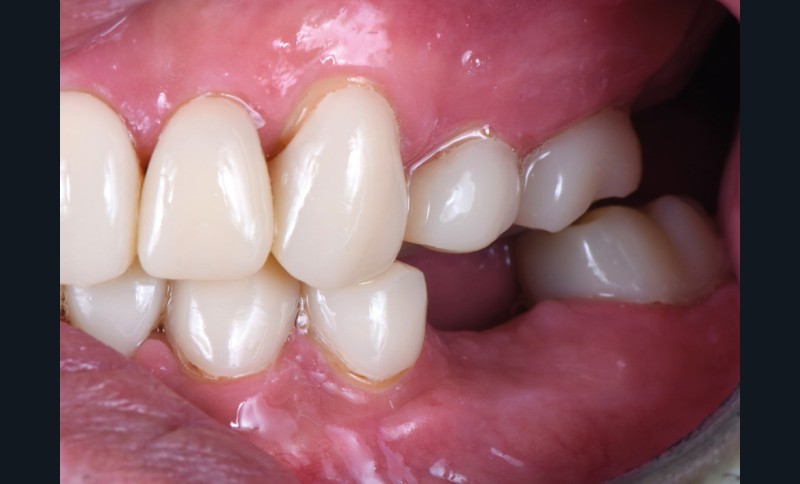

Au vu du contexte para-fonctionnel et de l’étendue de la perte tissulaire, des coiffes périphériques minimalement invasives ont été choisies afin de restaurer l’esthétique et la fonction. Actuellement, aucun consensus n’est fait sur le choix du matériau d’infrastructure à privilégier. Les matériaux hybrides usinables présentent des propriétés mécaniques, physiques et biologiques intéressantes en contexte d’usure sévère (e.g., module d’élasticité, résistance à la propagation de fêlures, facilité de réintervention). Une réhabilitation globale avec remontée de dimension verticale d’occlusion (DVO) par l’intermédiaire de coiffes composites renforcés en nano-céramiques est décrite.